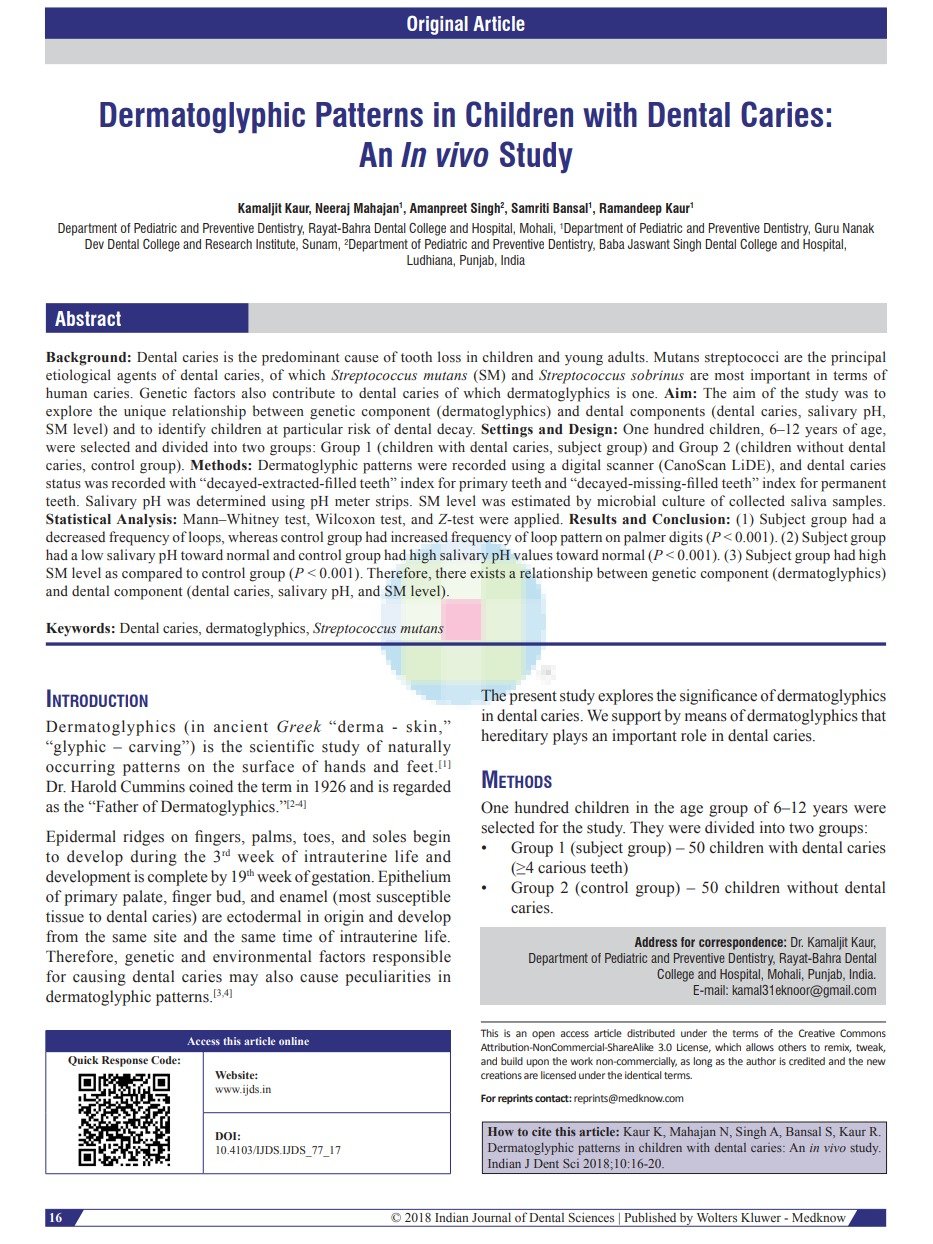

- Dr. Kamaljit Kaur